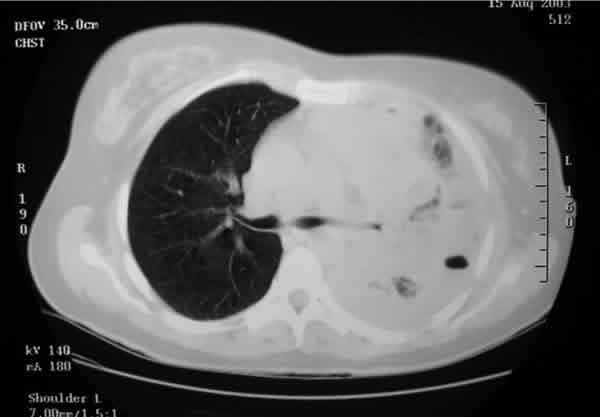

El mismo día que fue explorada en nuestro servicio, fue remitida al Servicio de Urgencias por haber debutado esa misma mañana con una disnea severa, le fue detectado un importante derrame pleural (fig. 3). Fue ingresada para ser estudiada y en el curso de apenas dos semanas se precipitaron los síntomas sistémicos debido a la enorme diseminación del tumor primario. El análisis histológico de una muestra obtenida mediante una broncoscopia, permitió identificar a un Carcinoma de Células Grandes pulmonar como tumor primario responsable de los múltiples focos metastásicos que la paciente presentaba y que en ese momento comprendía, además de la afectación ocular y torácica, masas cerebrales y hepáticas (figs. 4-6).

Fig. 4. En este corte de la TC se puede apreciar la

afectación masiva del hemitórax izquierdo por la masa tumoral y el derrame

pleural.